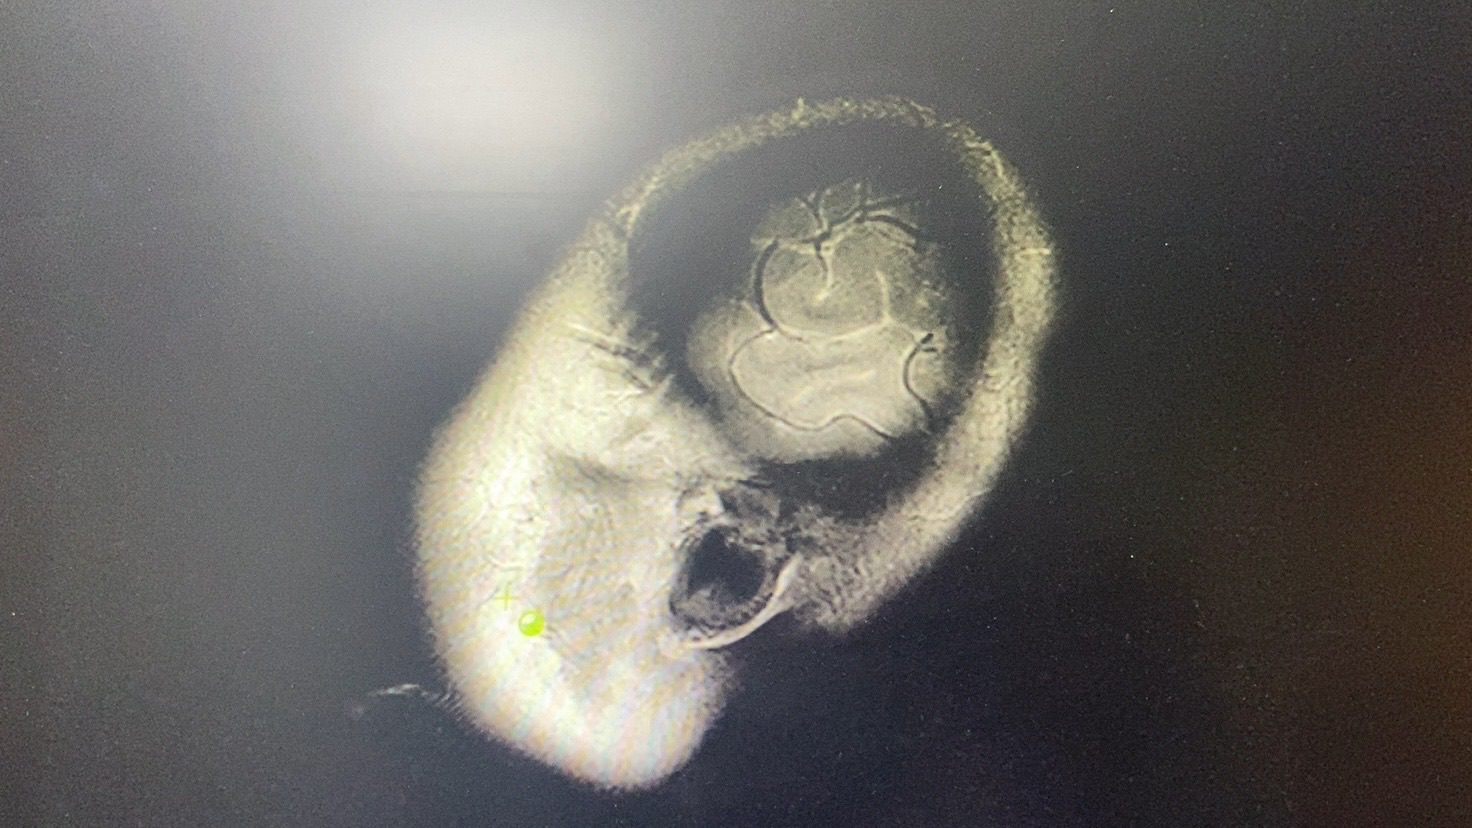

头MRI+DWI